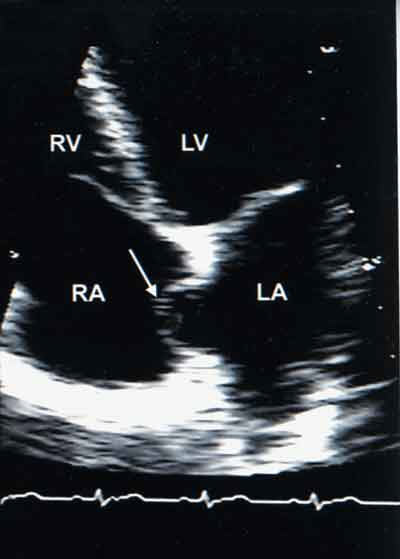

Мпп мжп

Мпп мжп 112 фото